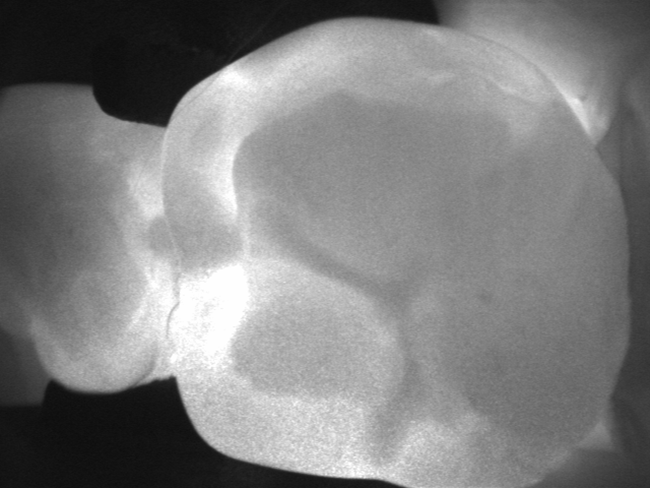

Dotychczas przeprowadzone badania kliniczne wskazują również na przydatność urządzenia DIAGNOcam (KaVo) (ryc. 4) w praktyce stomatologicznej w ocenie występowania próchnicy na powierzchniach stycznych. Porównanie metody prześwietlania tkanek światłem bliskiej poczerwieni ze zdjęciami skrzydłowo-zgryzowymi wykazało zgodność diagnozy w 95,3% przypadków występowania próchnicy w zębinie u pacjentów, u których nie stwierdzono utraty ciągłości twardych tkanek zęba i obecności wypełnień na powierzchniach aproksymalnych (14).

Ryc. 4. Diagnostyka próchnicy na powierzchni stycznej z użyciem urządzenia DIAGNOcam.